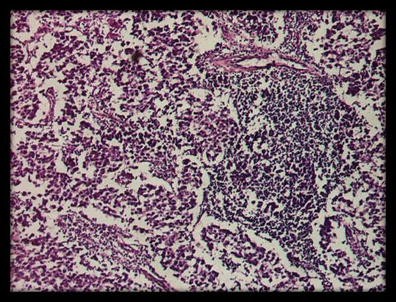

CRABP I expression in the cell cytoplasm of pNET G2 (Ki-67–9 %).:

figure b